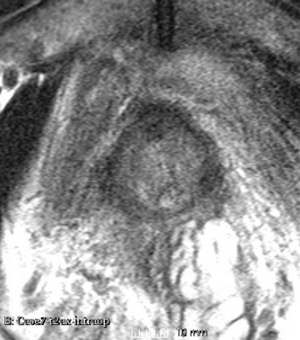

Case 8

Reference intraop volume

Reg Result Slicer 3.6 with ITKv3

Reg Result Slicer 4.4 with ITKv4

We used this sample data with Reader 1 segmentations to visually evaluate differences in the registration results. All three results of BRAINSFit with ITKv3 in Slicer 3.6 look reasonable. Using BRAINSFit with ITKv4 in Slicer 4.4 creates a reasonable result for Case 7, but look strongly distorted towards the edges of the bounding box in Case 8 and 9.